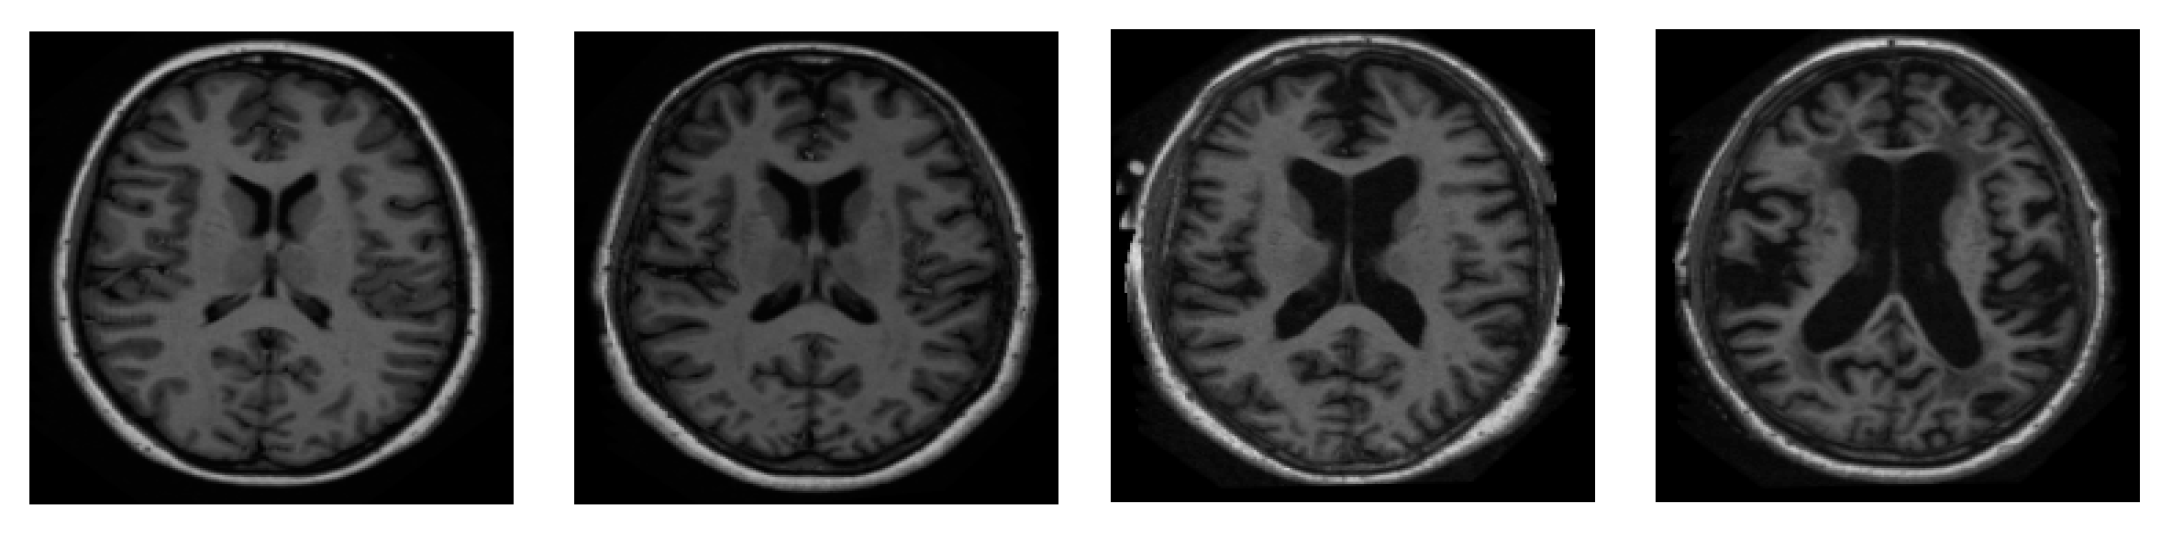

BraTS 19 has been utilized for brain MRI images with a focus on the segmentations of brain tumors on multi-model magnetic resonance imaging (MRI) scans. BraTS contains MRI.jpg format images of 240 × 240. It contains 3762 brain MRI images of both males and females (see Figure 3) [3].

Figure 3.

Sample images from BraTS.